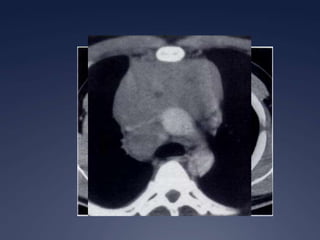

Quiste pericárdicoBrant and Helms:  389-416